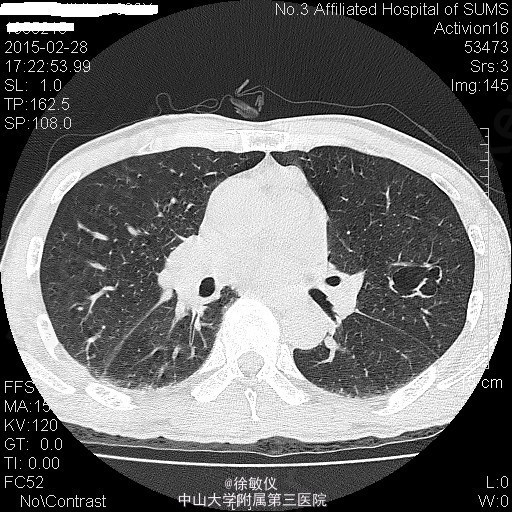

老年男性,主诉:咳嗽、咳痰2月余,头痛、纳差伴四肢乏力5天。 现病史患者2月余前无明显诱因出现咳嗽、咳痰,呈连声咳,咳白色稀薄痰,未予特殊治疗。5天前无明显诱因出现头痛,为右侧颞部持续性隐痛,尚可入睡,伴有纳差,四肢乏力。遂来我院门诊,查胸部CT示:1、左肺上叶尖后段空洞性病变;纵隔多发肿大淋巴结;中~大量心包积液。2、右肺中叶及双肺下叶少许慢性炎症。遂收入院。 查体:生命体征平稳,查体无特殊。 入院后予行心包穿刺抽液,心包积液检查:浆膜腔液总蛋白47.7g/L,乳酸脱氢酶306U/L,浆膜腔积液葡萄糖5.76mmol/L,白细胞计数2150X10E6,颜色黄色,粘蛋白定性试验+/-,红细胞计数1570X10E6,透明度微混,凝固物有凝块,淋巴细胞0.88,中性粒细胞0.12。血清 癌胚抗原>100ug/L。 血清乳酸脱氢酶:358U/L。 暂予头孢美唑钠(悉畅)注射剂2g Q12h,左氧氟沙星氯化钠(可乐必妥)注射液0.6g Qd抗感染治疗。 因患者诉头痛明显,行头颅MR提示:1右侧蝶骨嵴肿物,考虑脑膜瘤;双侧小脑半球及小脑蚓部肿物并双侧小脑半球脑沟脑回样强化,考虑转移瘤并脑膜转移,梗阻性脑积水。 诊断:1、心包积液 恶性肿瘤转移 2、高血压病 2级 高危 3、头部恶性肿瘤 颅内转移 4、脑膜瘤 5、肺部感染 患者肿瘤情况不明,出院后第二天因脑疝死亡。